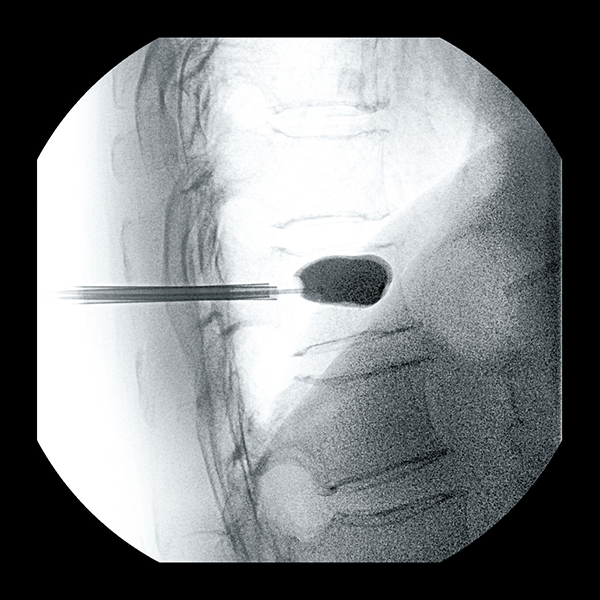

経皮的椎体形成術(BKP)

背部から撮影

側面から撮影

つぶれた椎体に風船を挿入して膨らませ、椎体を再建。その後、医療用セメントを充填して骨強度を保つ